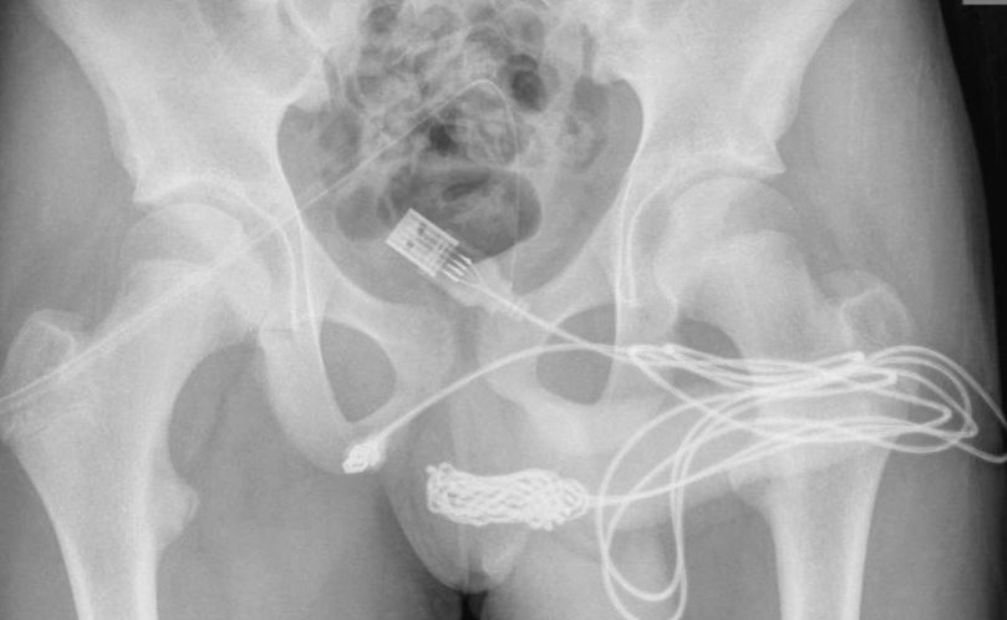

Pasi u krye një rreze X që zbuloi madhësinë dhe pozicionet e sakta të fishës, adoleshenti u dërgua në kirurgji. Nuk kishte komplikime gjatë operacioniet dhe adoleshenti u lirua nga spitali të nesërmen.